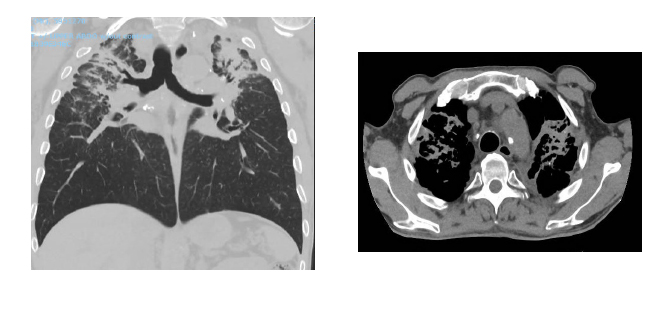

CT scans of a tunneller diagnosed with silicosis. The light grey areas at the top part of the lungs represent severe scar-tissue. UNSW Sydney/Deborah Yates